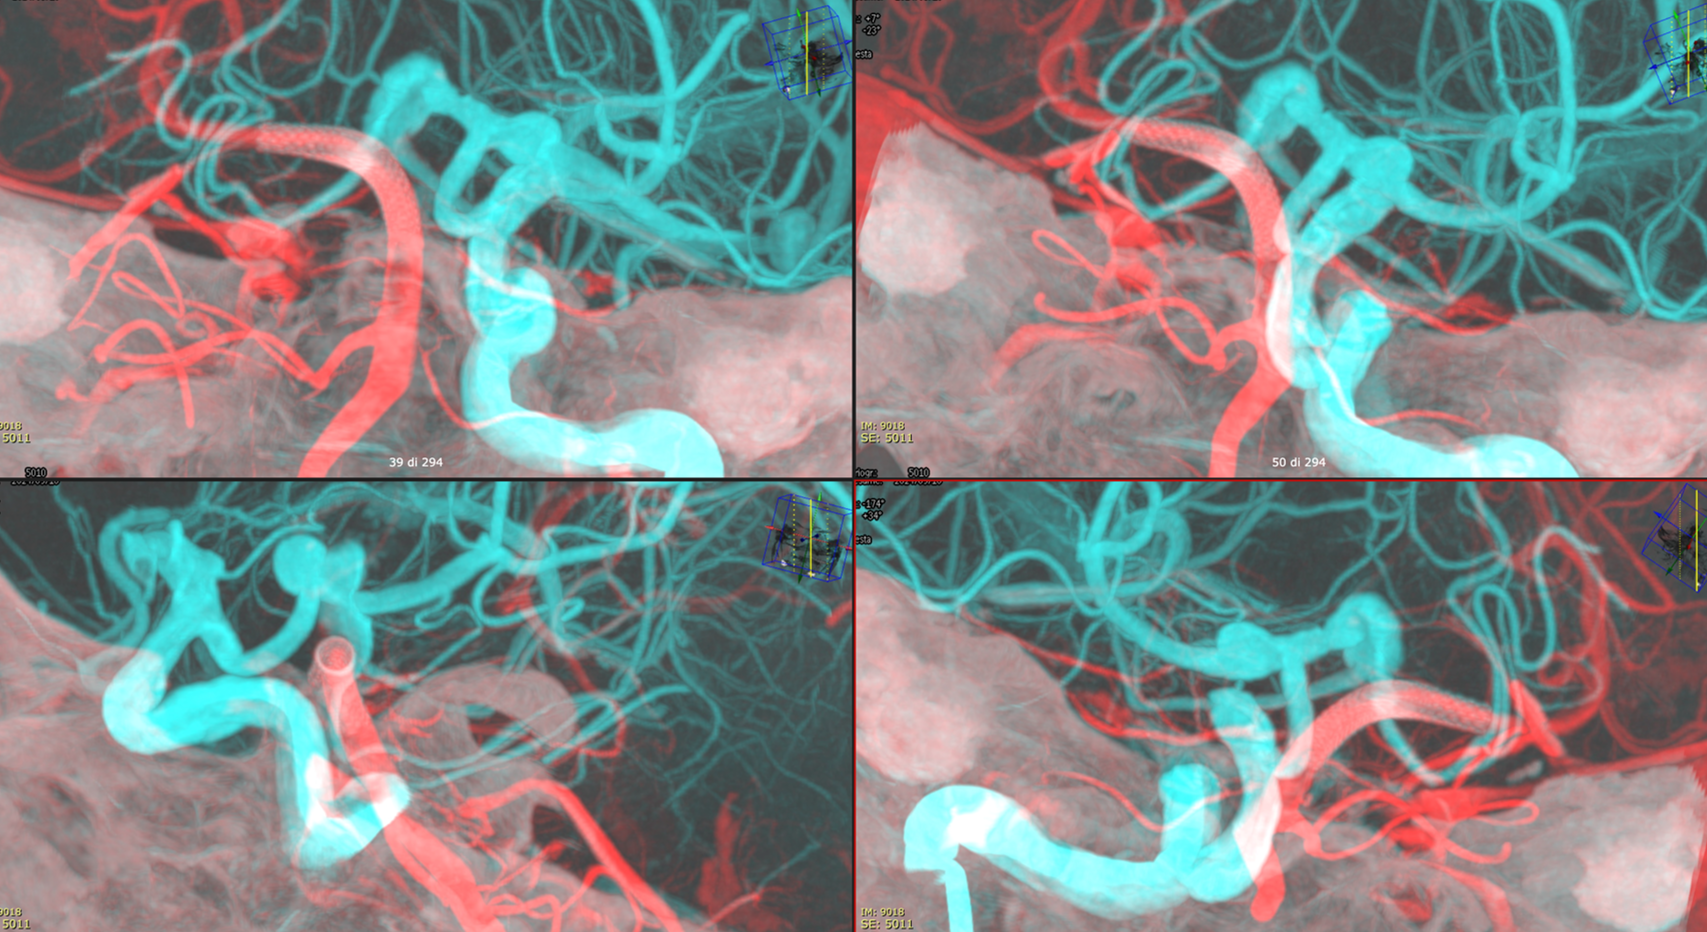

Noncontrast / dry Vaso-CT, 22 cm FOV 20 seconds acquisition, followed by a secondary reconstruction with 50% FOV and 5123 resolution; Thick MIP.

Two Lvis EVO have been used (in inverse Y or ? lambda shape). The first from the left PCom into the left SCA. The second from the left PCom into the right SCA. Another microcatheter in jailed in the aneurysm for the subsequent coiling.

There are no labels or arrows on any of the devices. If you are not sure what is going on, we suggest studying the images until you do.

Thick MIP reconstruction of a Vaso-CT acquired with manual injection of right vert and left ICA at the same time. Vaso-CT, 22 cm FOV 20 seconds acquisition, followed by a secondary reconstruction with 67% FOV and 5123 resolution; Thick MIP.

The procedure finished with coiling of the basilar tip around the stents and PTA of right SCA stent at the crossing of the other stent

Vas is das? You figure it out…

Post Rx. The key to this procedure, other than sophisticated understanding of the problem and the materials to be used, is a consistently effective antiplatelet state. Doing this without IIbIIIa in the lab for example risks major disaster.

At the 8 months follow-up, after passing from DAPT to SAPT, the aneurysm became smaller, with corresponding clinical improvement.

This is a key point — the success of treatment in aneurysms of this type is judged by cross-sectional imaging, not angio. With aneurysm shrinkage a good angiogram is guaranteed, while there are many examples of good-looking angiograms with moribund patients.